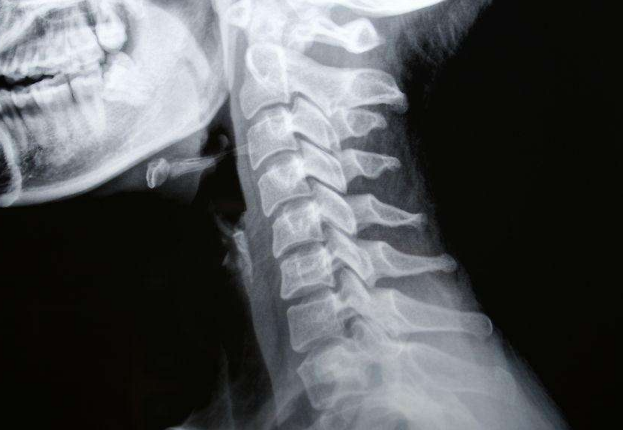

X線、CT、MRI檢查

頸椎病圖片